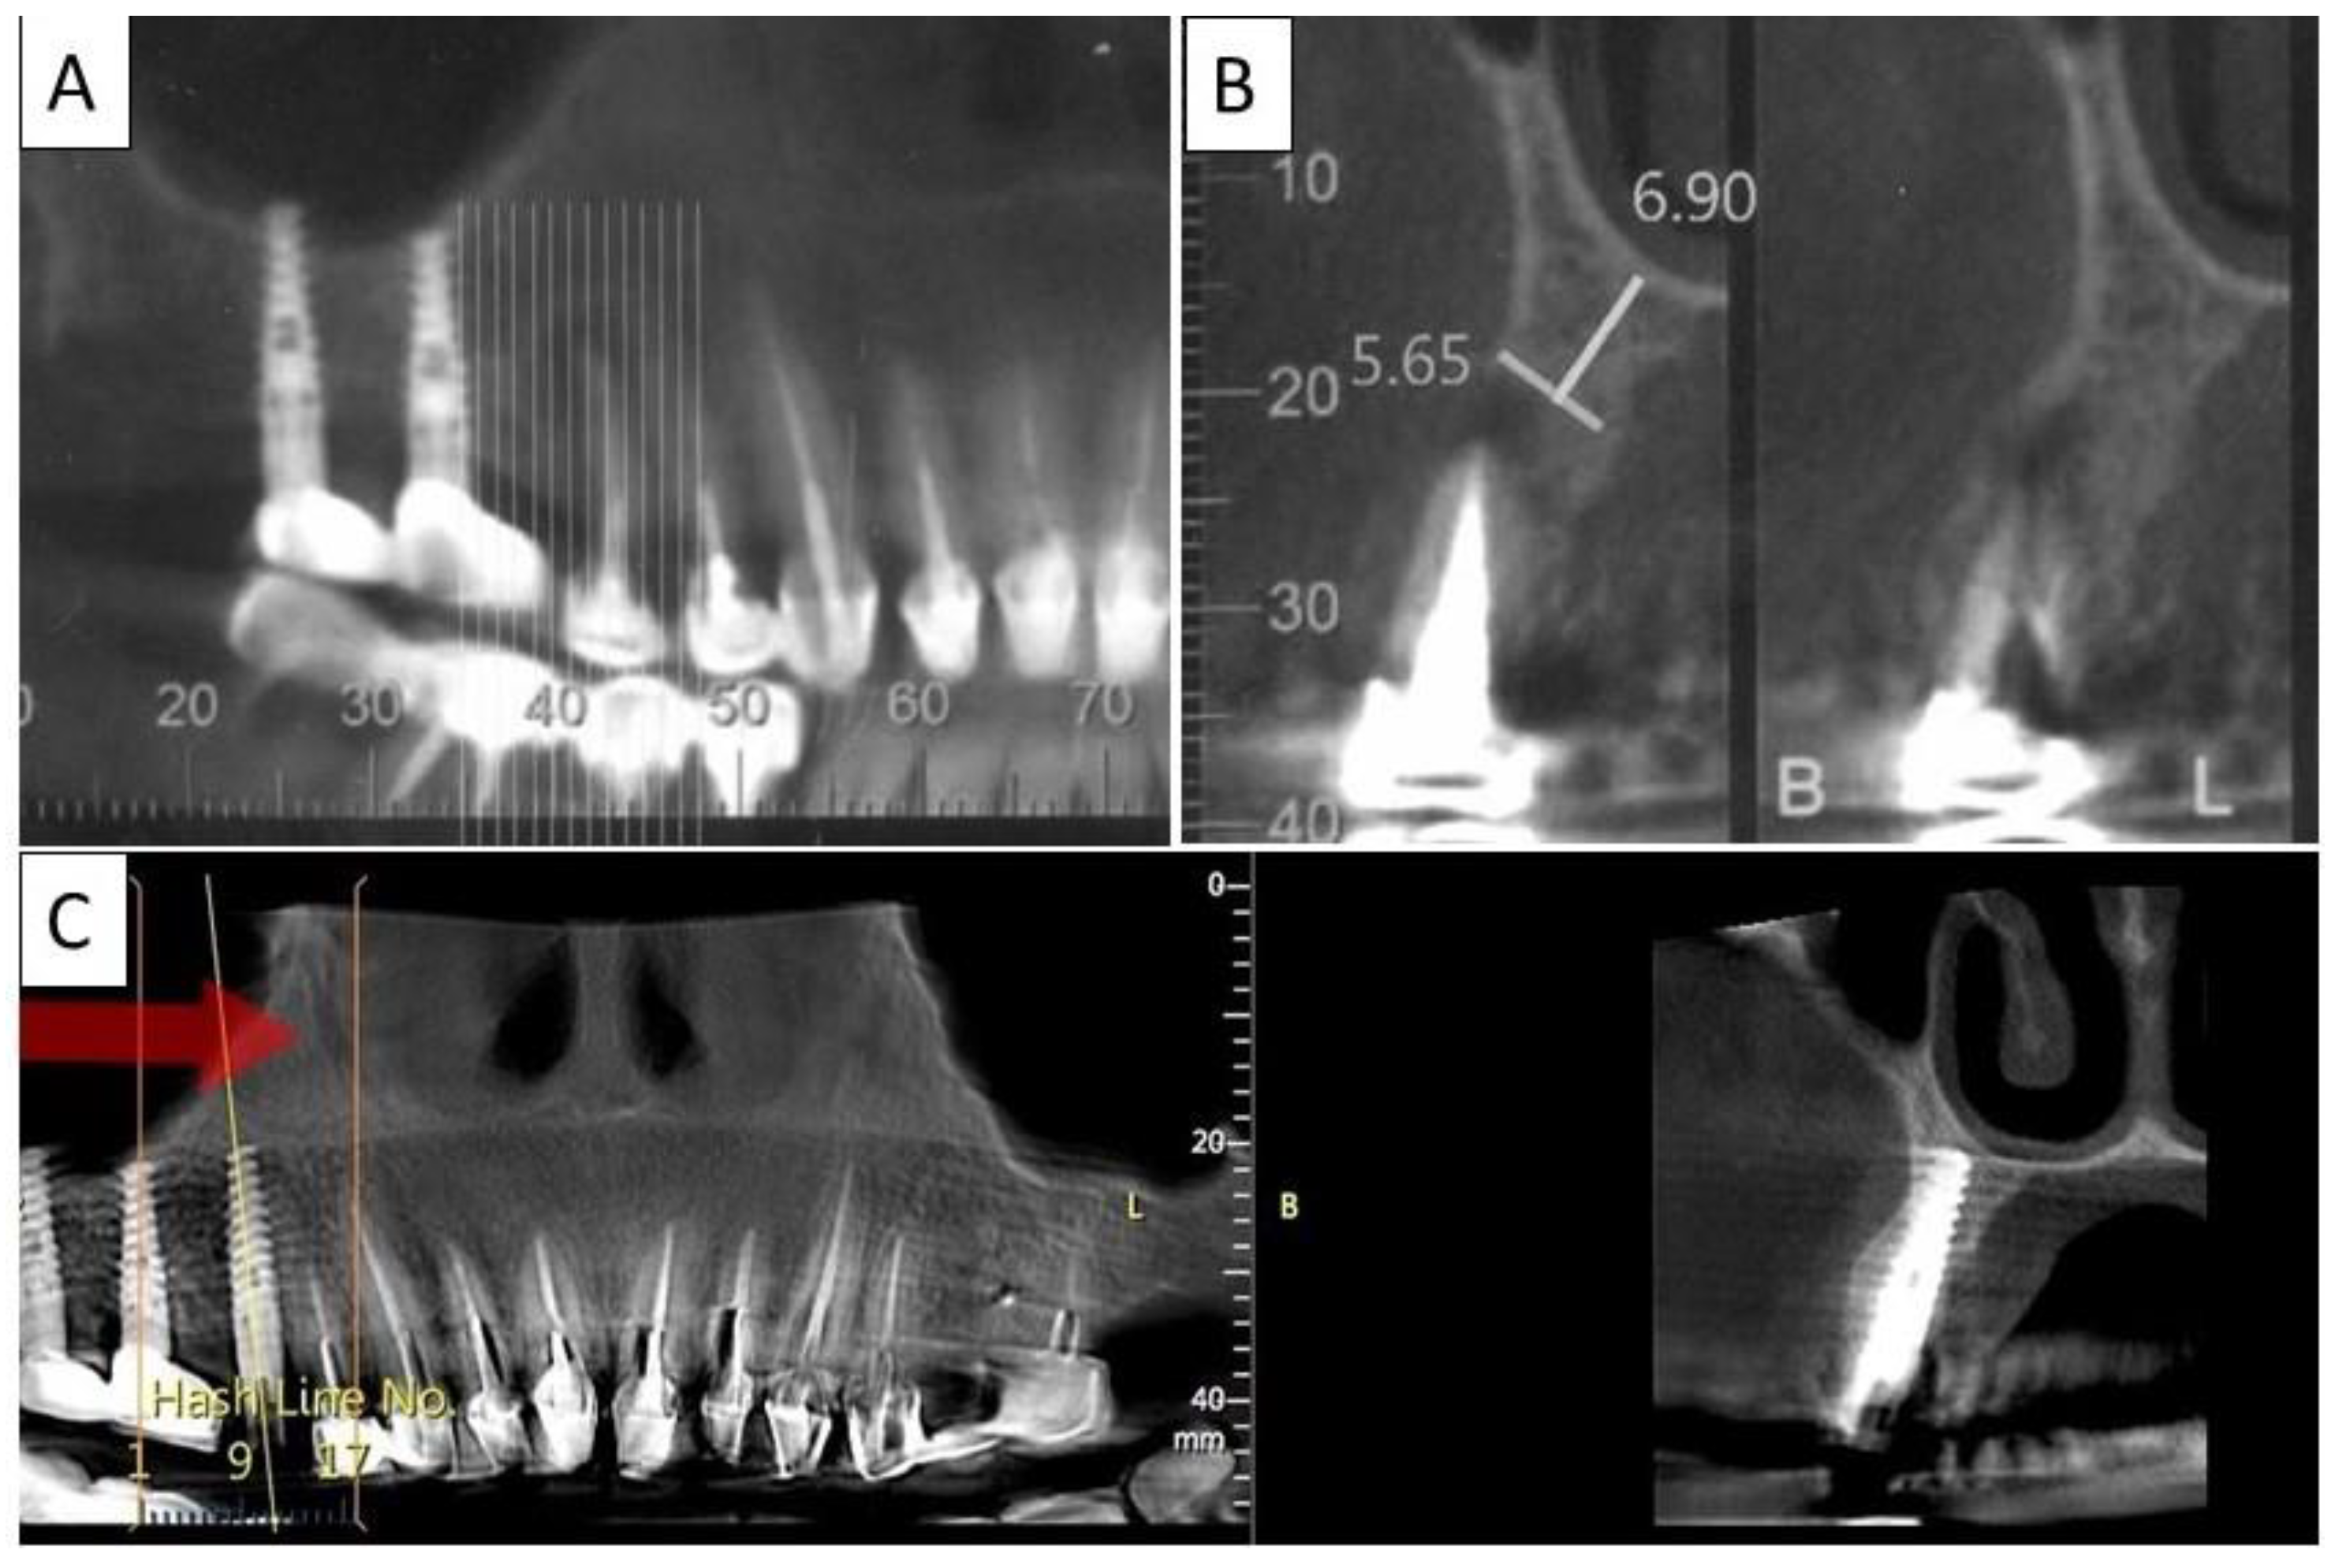

Figure 7.

(A) Panoramic CBCT section shows bone loss around tooth 21. (B) Sagittal CBCT section of the area around tooth 21 shows extensive buccal bone loss. (C) A sagittal CBCT section shows the implant placed at site 21 with a restored cortical buccal plate. (D) Panoramic CBCT section shows bone formation around the implant in area 21.